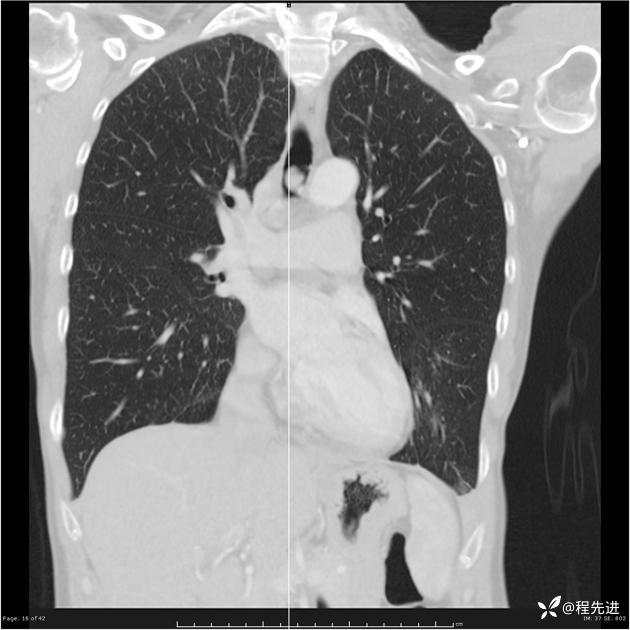

病例女,53岁,气管、左主支气管、下叶支气管内结节,乳头状瘤?期待你的精彩解读

女,53岁

乳头状瘤?